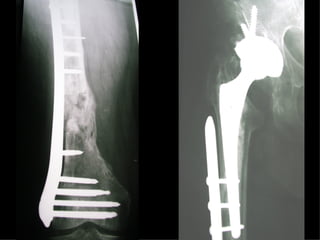

Dal Gennaio 2000 al Dicembre 2005 27 placche LISS di femore

INDICAZIONI COMUNI Fratture sovracondiloidee Fratture intercondiliodee Fratture diafisarie distali PARTICOLARI Fratture con grave osteoporosi Fratture periprotesiche

VANTAGGI CHIRURGIA MININVASIVA Mini Open Inserimento della placca sottocutaneo per scivolamento Viti percutanee Preservazione dei tessuti molli Ridotto danno vascolare Rapida ripresa funzionale

LISS  NCB

NCB